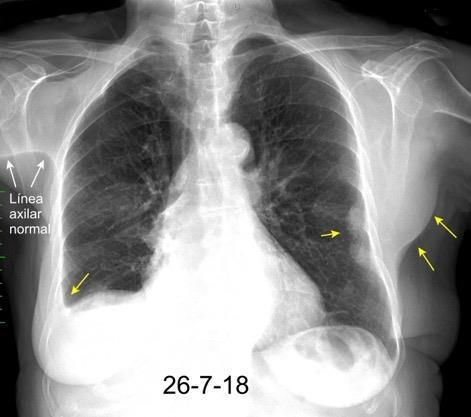

Pliegue axilar Normal

Rehúsa cirugía

2011. Acude por masa axilar

Linfoma NH de cél. B. Invasión Transtorácica.

Afectación axilar